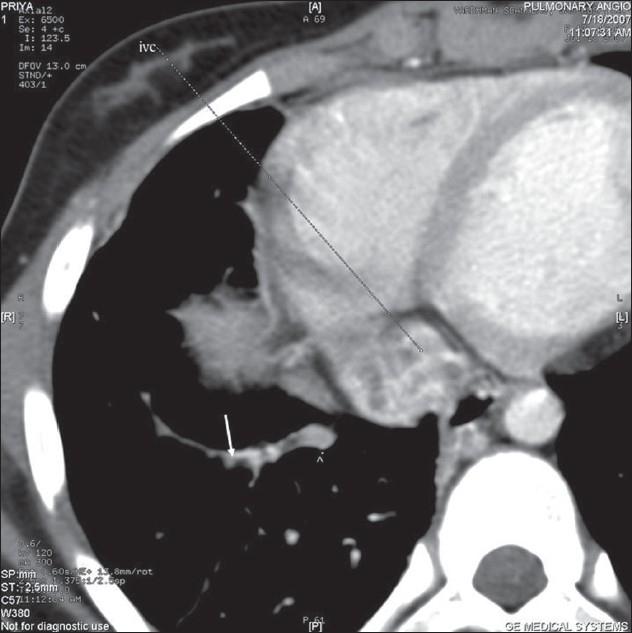

Scimitar syndrome is a rare congenital disorder. It has a varied presentation. In adult life, it usually presents either as recurrent chest infection and/or exertional dyspnea. Pulmonary artery hypertension and hemoptysis both are uncommon features of this syndrome in adult life.

弯刀综合征是一种罕见的先天性疾病。其表现多样。在成年期,它通常表现为反复的胸部感染和/或劳力性呼吸困难。肺动脉高压和咯血在成年期都是该综合征不常见的特征。